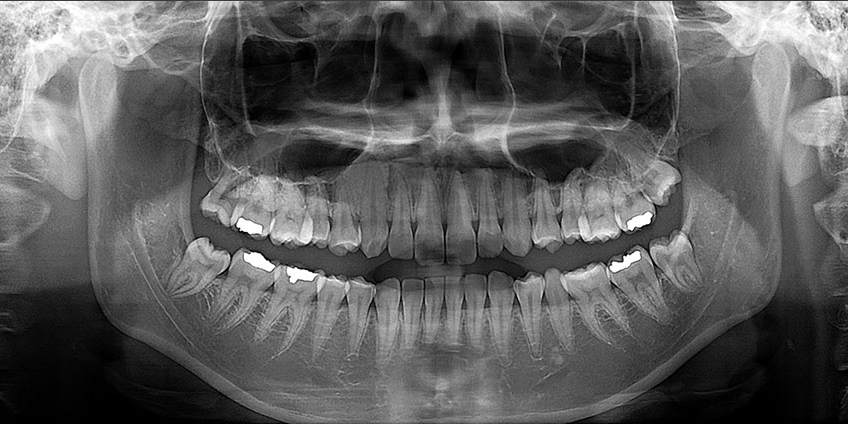

See where you focus

Light guided free FOV

More detail, more confidence

70μm resolution @ 4x3cm

Image reconstruction in 6 seconds

Superior image processing technology